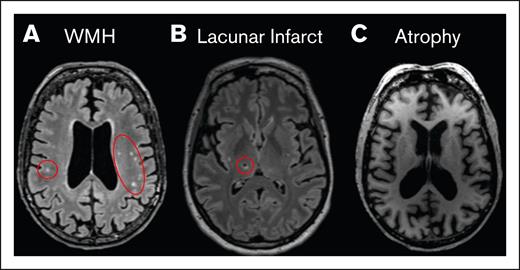

Representative image of radiologic findings. (A) T₂-FLAIR image of multiple WMHs (red circles). (B) T₂-FLAIR image of a chronic lacunar infarct (red circle). (C) MPRAGE image showing whole-brain volume loss (atrophy). MPRAGE, magnetization-prepared rapid acquisition with gradient echo; WMH, white matter hyperintensities.